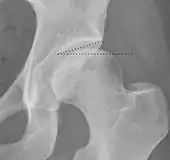

Measurements of impingement on X-ray.[notes 1][20]

MeasurementImageTargetNormal value

Tönnis angle Slope of the sourcil (the sclerotic weight-bearing portion of the acetabulum) 0 to 10°

• >10° is a risk factor for instability

• <0° is a risk factor for pincer impingement